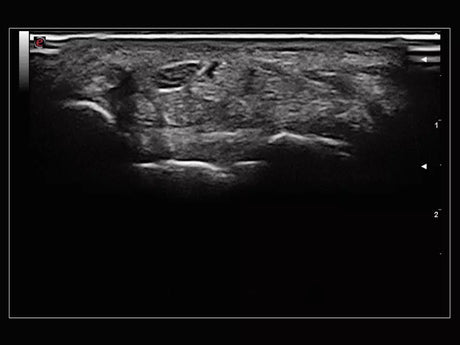

La qualité d’image est au cœur de la philosophie Esaote. Grâce à ses sondes de dernière génération et à son traitement du signal avancé, la marque permet une visualisation fine des structures anatomiques, même les plus profondes. Leurs échographes intègrent des écrans tactiles haute résolution, une interface claire et une connectivité complète, favorisant un flux de travail rapide et efficace.

Un gynécologue privilégiera un échographe offrant une résolution d’image très fine et une compatibilité avec des sondes endocavitaires. Un kinésithérapeute ou un médecin du sport recherchera plutôt un appareil portable, léger et rapide à mettre en route. Les praticiens généralistes apprécieront la polyvalence et la facilité d’entretien, tandis que les vétérinaires auront besoin d’un système robuste et facilement transportable.